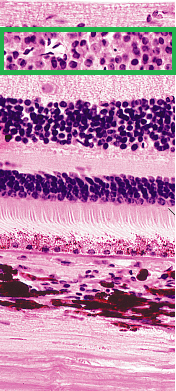

Marque la opción correcta de acuerdo a estructura y capa señalada

Image:

9c1bb4e3-981a-4983-9ac4-0592ca729604 (image/png)

Answer

Retina, capa de fotorreceptores

Coroides, capa de fotorreceptores

Retina, capa plexiforme externa